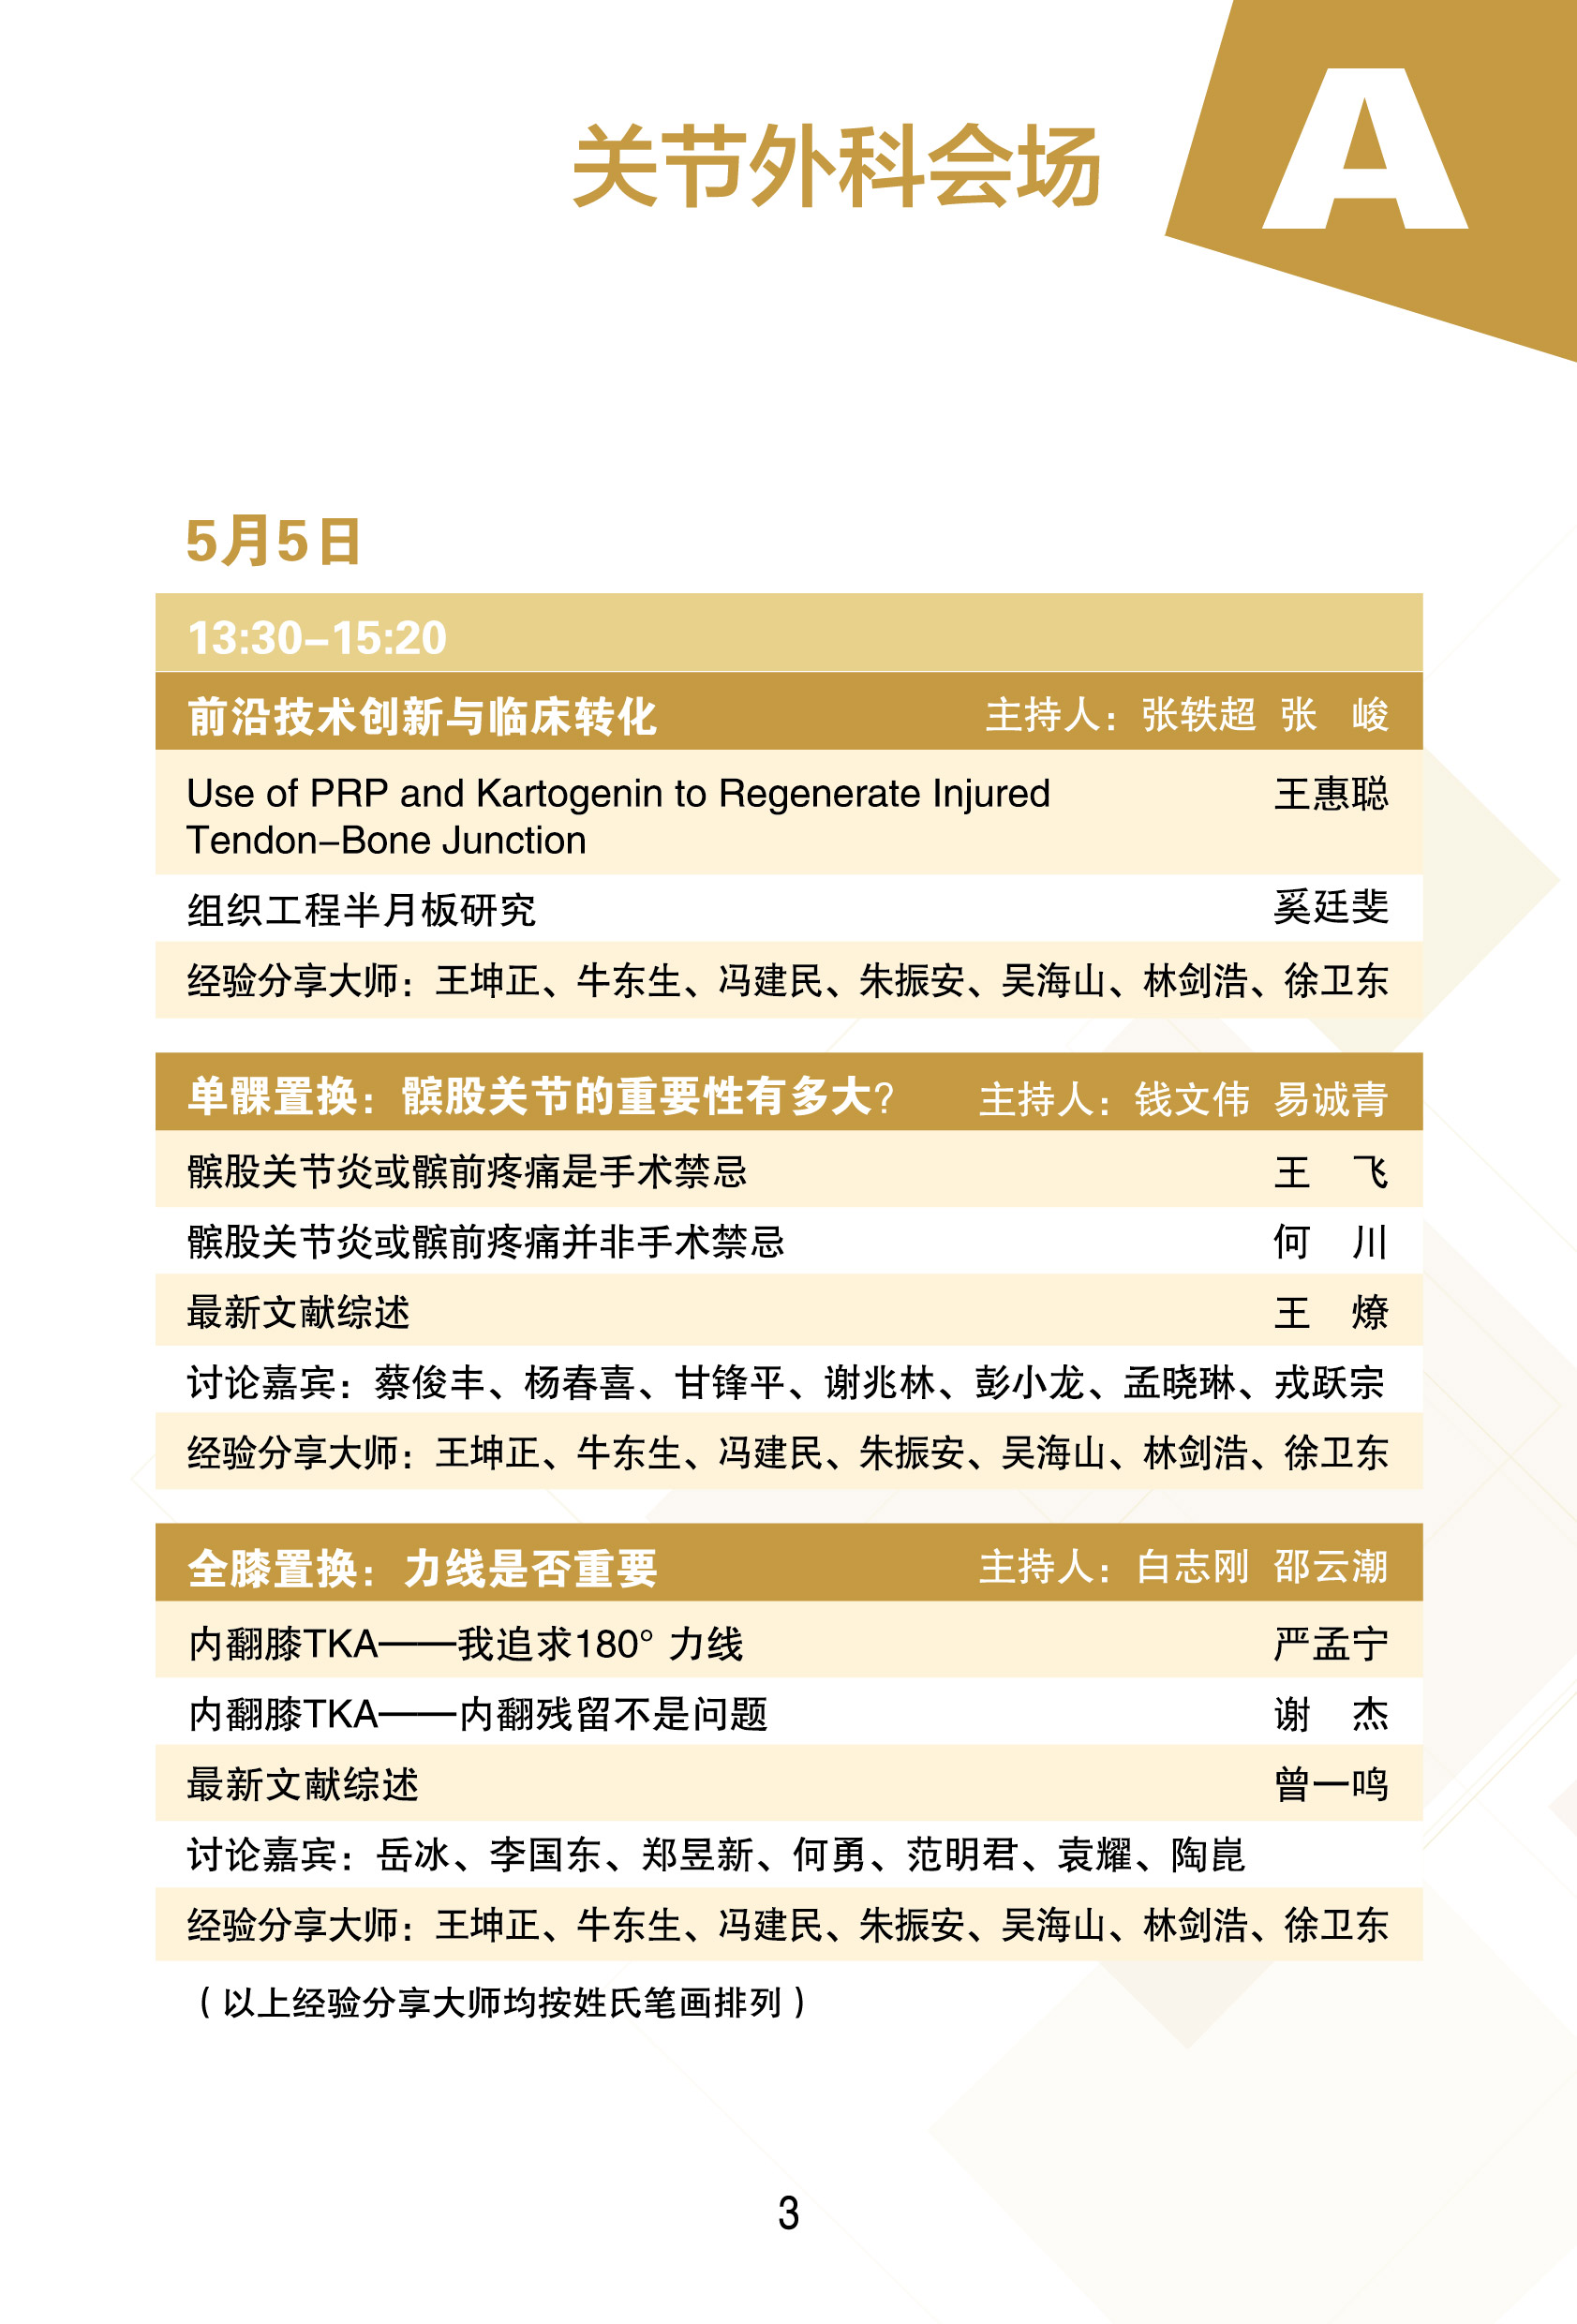

第十二届上海国际骨科前沿技术与临床转化学术会议 学术日程